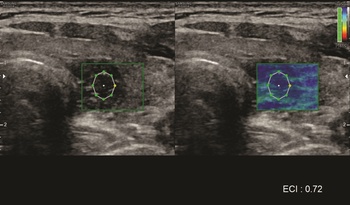

A sugárterheléssel nem járó ultrahangvizsgálatokat számos területen alkalmazzák az ikerkutatásban (1. és 2. a, b ábra), a policisztás ovárium szindrómától kezdve a szaruhártya megítélésén át az érelmeszesedés vizsgálatáig széleskörűen alkalmazott módszer. Néhány ultrahangos ikervizsgálatot emelnénk ki ezek közül. A finn ikerregiszter hüvelyi ultrahang vizsgálattal ítélte meg a méh gyakori jóindulatú daganata, a mióma előfordulását. A miómák száma gyenge genetikai meghatározottságot igazolt, míg a miómák előfordulása összefüggést mutatott a magasabb testsúly-testmagasság indexszel (Luoto et al., 2000). A fejlődő országokban egyre gyakrabban előforduló epekövesség molekuláris patogenezise nem teljesen ismert. A svéd ikerregiszter munkatársai epekövességben szenvedő ikerpárok – részben ultrahangos – vizsgálata során kimutatták, hogy az ABCG8 D19H génvariánst hordozó egyéneknek nagyobb az epekövességre való hajlamuk (Katsika et al., 2010). A hazánkban is minden negyedik felnőttet érintő nem alkoholos zsírmáj hátterében additív genetikai hátteret nem igazolt vizsgálatunk, közös (74,2%) és egyéni (25,8%) környezeti tényezők állnak a betegség hátterében (Tárnoki et al., 2012). Szintén hazai ikermintánkon ultrahanggal vizsgáltuk a veseparenchima vastagságában szerepet játszó genetikai meghatározottság mértékét, mely korra és nemre korrigálva 0%-os volt, a közös (30%) és egyéni (70%) környezeti tényezők hatásai domináltak. Eredményeink az életmód, illetve a primer prevenció fontosságára hívták fel a figyelmet (Tárnoki et al., 2013).

1. ábra. Magyar ikeralany pajzsmirigy ultrahang elasztográfiás mérése, melynek során a göbök elaszticitási indexét vizsgáltuk